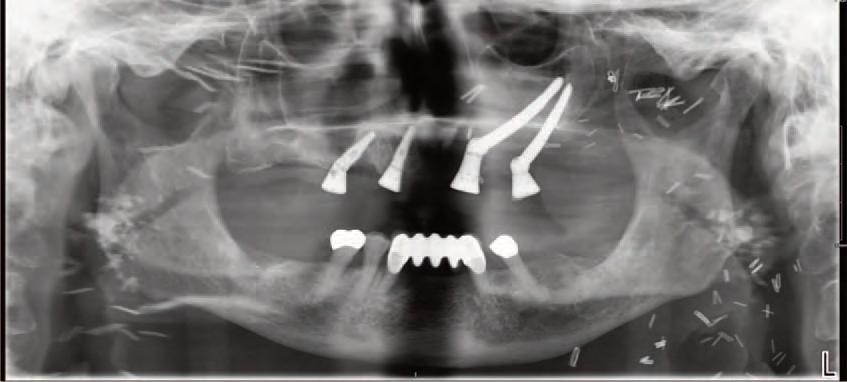

The zygomatic implant perforated (ZIP) flap for rehabilitation of patients with midfacial oncology defects: a report of three cases B. Martin, E. Cotter, C. Bowe, J.E. O’Connell

Issuu converts static files into: digital portfolios, online yearbooks, online catalogs, digital photo albums and more. Sign up and create your flipbook.